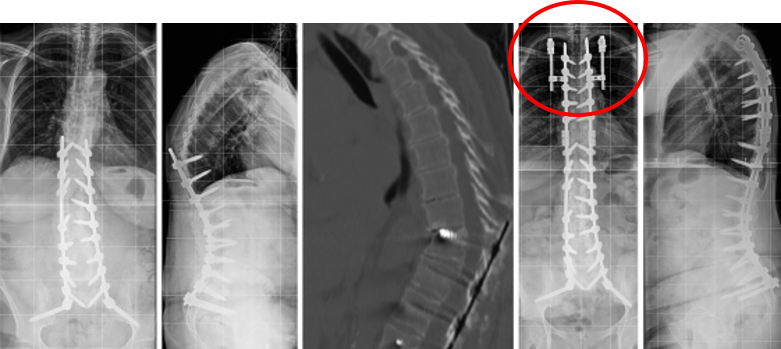

T10骨盆固定,出现交界性后凸

行翻修手术:T9/10SP截骨,延长到T4固定,预防性双侧肋骨固定(VEPTR)

图32-33 肋骨固定

(4)Topping-Off 技术

Topping-off技术又称为融合区+上位邻近节段动态稳定技术

即从融合节段向活动节段过度的手术,旨在融合节段和活动节段之间形成缓冲区,降低邻近节段应力集中

图34-35 据文献报道,可应用一种环形和夹层胶带的技术,以重新创建一个有机后张力带UIV和UIV+1之间将上下棘突绑扎后,增强交界区后方张力带结构强度